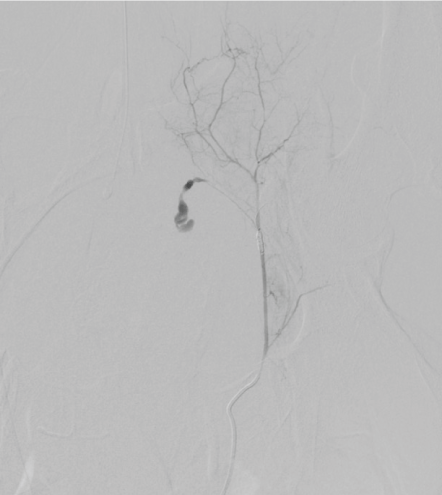

Seven hours after undergoing an uneventful TVT insertion under local anesthesia a 55-year-old non-obese para 2 woman was brought to the emergency department complaining of lower abdominal pain and vertigo. On physical examination, she was alert and aware, but pale, peripherally cold and hypotensive (blood pressure was 80/30 and pulse = 55/minute). Apart from medical treatment for hypertension, she was healthy. Prior surgical history included an appendectomy only. On suspicion of intraperitoneal bleeding, laparoscopic evaluation was performed showing a large hematoma retropubically and on the posterior abdominal wall and after conferral with a vascular surgeon, the decision was made to perform arterial embolization. The subsequent angiography localized significant bleeding from the right obturator artery; an anterior branch of the internal iliac vessel (Figure 1) and a retropubic hematoma 17.5 cm × 10.0 cm in size (Figure 2). The patient was treated by selective embolization with coils of the right obturator artery (Figure 3) and her vital signs remained stable after the procedure. Five days postoperatively, the patients presented with fever of 38.9 ºC and diffuse lower abdominal pain. She received intravenous broad-spectrum antibiotics, the pain abated and an enhanced Computed Tomography (CT) scan revealed a reduced hematoma sized 11 cm × 6 cm. To prevent formation of an abscess and due to ongoing fever (temperature up to 38.9 ºC) laparoscopic evacuation of the hematoma was performed with a total blood loss of 1000 ml on postoperative day 10. Because the upper part of the tape had loosened from the tissue and was visible intraperitoneally, this part had to be removed.

Figure 1: Pelvic arteriography before embolization of the right obturator artery. View Figure 1